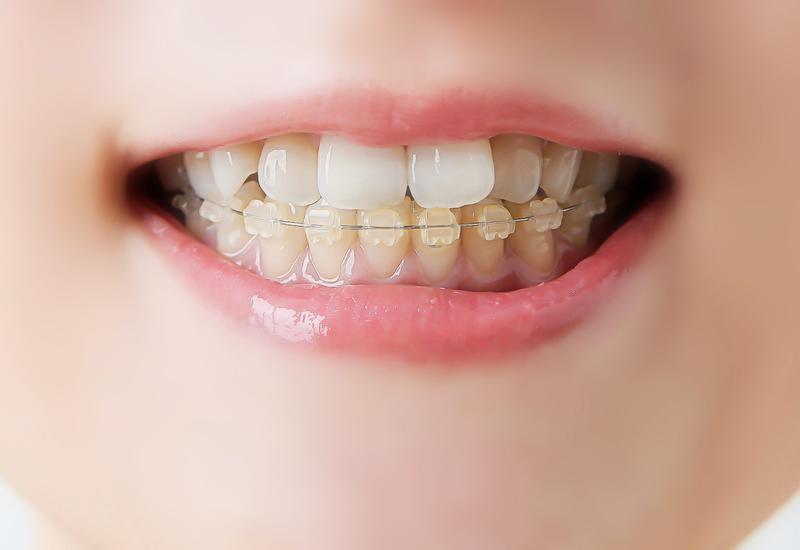

マルチブラケット

(=従来の針金)矯正

歴史のある「ワイヤー矯正」で、

難しい歯並びにも対応しやすい

歯の表面に「ブラケット」というボタンのような装置をつけ、そこにワイヤーを通して歯を引っ張る、昔からある治療法です。

治療中の見た目やご自宅で行うこと

見た目

装置が見えます。最近は白い装置もありますが、近くで見ると分かります。

ご自宅で行うこと

装置の周りに食べ物が詰まりやすいので、丁寧な歯磨きが必要です。

装置の特長

歯を大きく動かしたり、複雑なねじれを治したりするのが得意です。

マルチブラケット矯正が難しい歯並びに対応できる理由として、「歯を動かす力の強さ・細かな調整力・装置の固定力」という点が挙げられます。